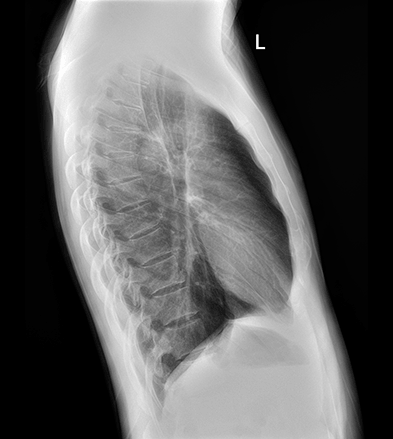

平板探测器

超高像素

高清点片